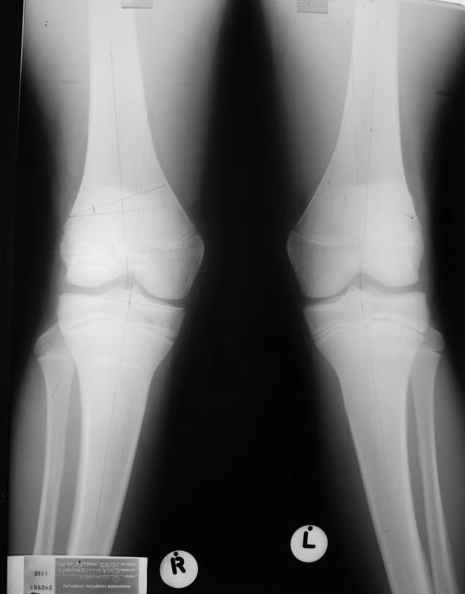

Re: Посстравматическая деформация колена

Как вариант решения прогрессирующей вальгусной деформации коленного сустава я бы предложил косую остеотомию дистального отдела бедра с фиксацией пластиной и компрессирующим винтом.

Взгляните на снимки , может быть это вам поможет.

Около 5 лет применяю этот тип дистальной остеотомии бедра для коррекции механической оси Н/К ( более 20 случаев) - достаточно эффективная операция.